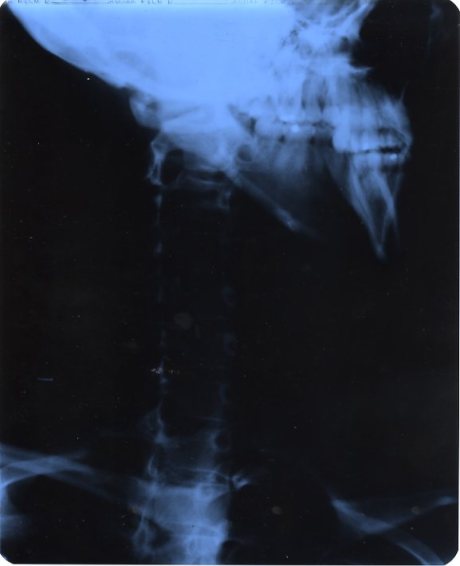

My Mom decides to send me to the Orthopedics hospital since they specialize in stuff like carpal tunnel. I get x-rays, cat scanned up and they determine that my neck is too straight. I’ve lost my natural curvature in the vertebrae of my neck causing pressure on my nerves, therefor giving me carpal tunnel.

Straight as an Arrow